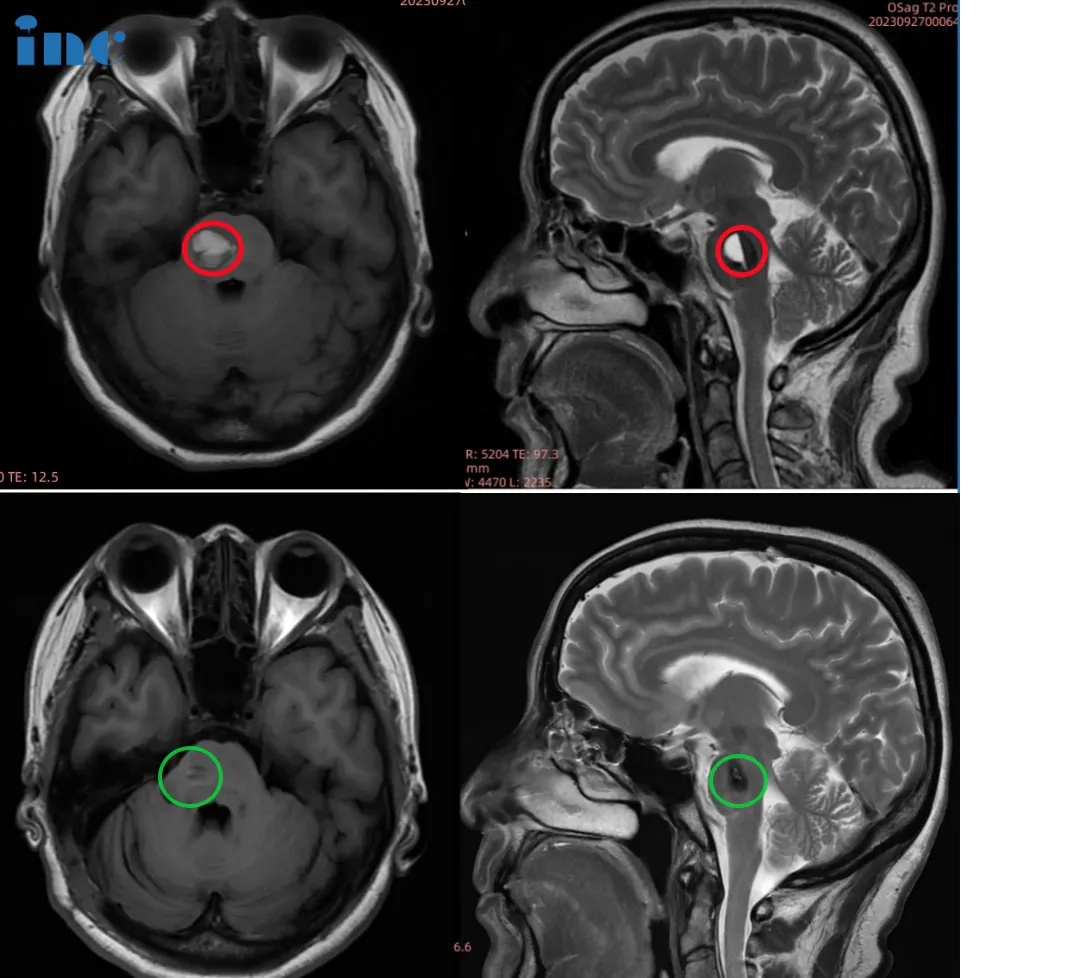

18岁男孩—脑干海绵状血管瘤

“我们又到了北京,医生看了一下,说这个没法动手术的。只要动是90%以上会瘫痪。别说90%,50%我也不敢让他动,因为孩子才18岁。

原先他生病的时候喝水都漏,现在吃饭喝水啥问题都没有。所以巴教授的技术真的厉害,所以找到他我们也算是挺幸运的,真是有好多人真找不着。原来右边麻没有劲,现在右边也有力量了。说话也清楚了,没有大舌头了。现在状态明显比手术之前好,是好的结果。现在说话也清楚了,能卷翘舌了,数字也能说清楚,10和4。”